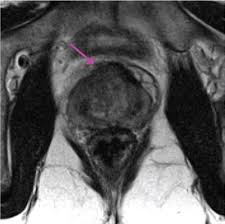

Transitional Zone Prostate Cancer Mri - Multi Parametric Mr Imaging Of Transition Zone Prostate Cancer Imaging Features Detection And Staging / Here are 10 more facts about prostate cancer.

Https Epad Uroweb Org Wp Content Uploads 3 Role Of Mri J Barentsz Pdf

Https Epad Uroweb Org Wp Content Uploads 3 Role Of Mri J Barentsz Pdf from